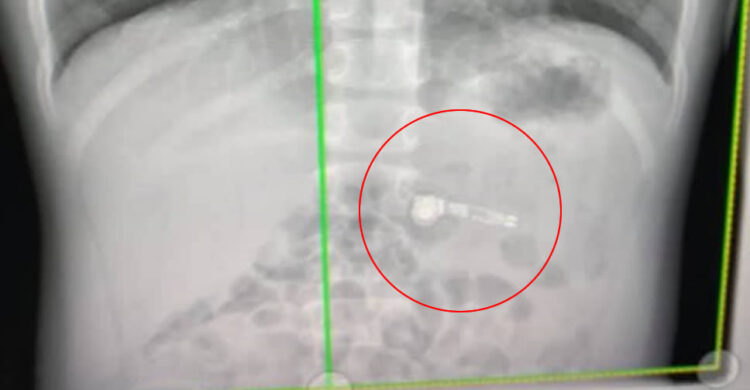

Kiara Stroud คุณแม่ของเด็กชายวัย 7 ขวบ พบว่าลูกของเธอได้เผลอกลืน AirPods ลงไป จึงได้รีบนำตัวส่งโรงพยาบาล โชคดีที่ไม่ติดคอ ซึ่งอาจเป็นการสูญเสียครั้งใหญ่ และหลังจากผ่านการเอ็กซเรย์ ก็พบว่ามี AirPods ข้างหนึ่งอยู่ในท้องของเด็ก

คุณหมอที่ได้เห็นภาพเอ็กซเรย์ ยืนยันว่าลูกชายวัย 7 ขวบของ Kiara Stroud กลืน AirPods ลงไปในปากจริงๆ และหวังว่าเด็กจะสามารถขับถ่าย AirPods ออกมาได้เอง โดยไม่ต้องทำการผ่าตัดใดๆ